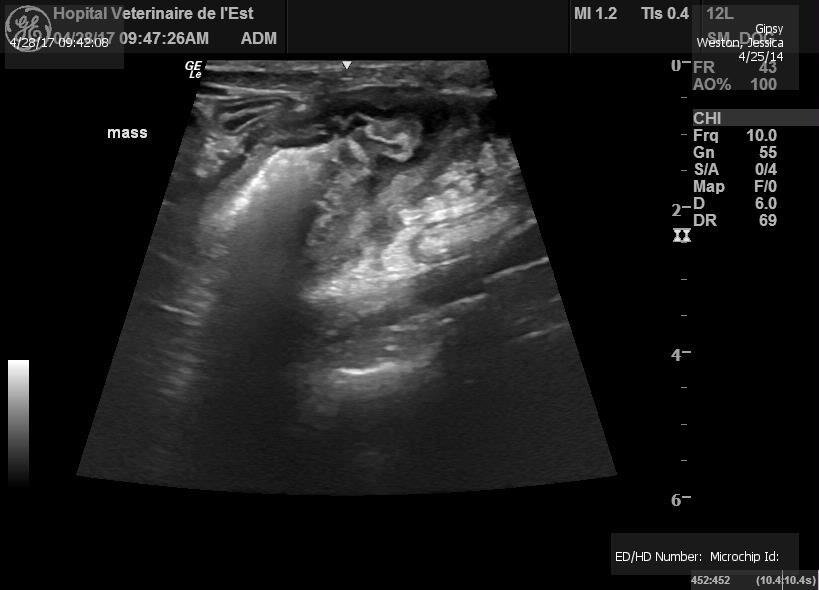

Gypsy has been loosing weight since Christmas. I figured she was depressed, this being her first winter in Canada. When she started loosing her appetite, I decided to bring her in for some test. The vet felt a mass in her stomach so we did some bloodwork and xrays. They weren't conclusive so they sent her for an ultrasound. The ultrasound confirmed she had a 2.5 cm cancerous mass growing in her abdomen. If left untreated, they don't expect her to make it through the summer

Here are pictures of Gypsy fighting Cancer 28/05 :

She has lost all her weight and muscle mass. She is just as skinny as the day we found her. Her energy levels are still high and the vet confirms she is not yet suffering.